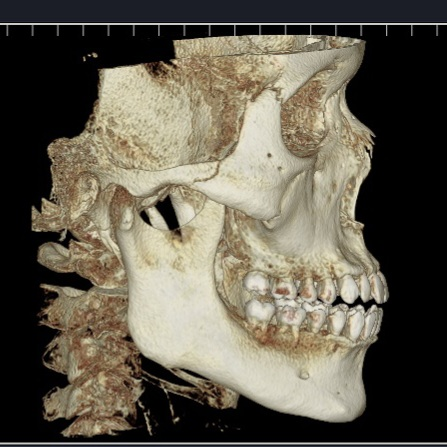

돌출입과 부정교합으로 인해

입이 벌어지게 되면 구호흡을하는 경우도 있습니다.